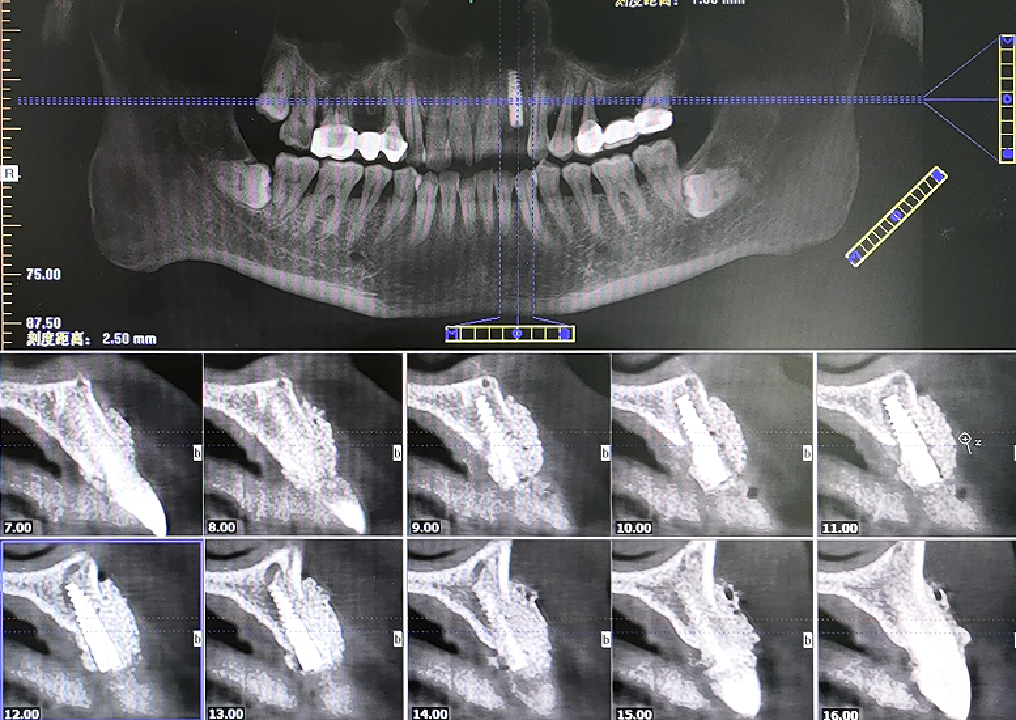

术后即刻CBCT

术后CBCT

术前术后CBCT对比

唇侧过量植骨希望最终能够实现存量骨组织>2mm。

术后4.5个月CBCT

术后即刻与术后4.5个月CBCT对比

可见种植体唇侧顶端有一定骨粉吸收,但仍在预期范围内。